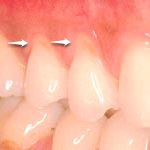

| 症例 6 | |

|---|---|

| 歯と歯肉の境目が、凹んでくることはよくあります。原因は歯ブラシによる場合と、強い噛み合わせによる場合があります。 この凹みは、知覚過敏の原因となることが多く、知覚過敏に対する治療としてレジン治療を行うこともあります。 レジン治療は保険適用。治療のための通院回数は1回です。 | |

| Before | After |

![]() | ![]() |

| 矢印の部分の歯と歯肉の境目が凹んでいます | レジンで修復致しました |